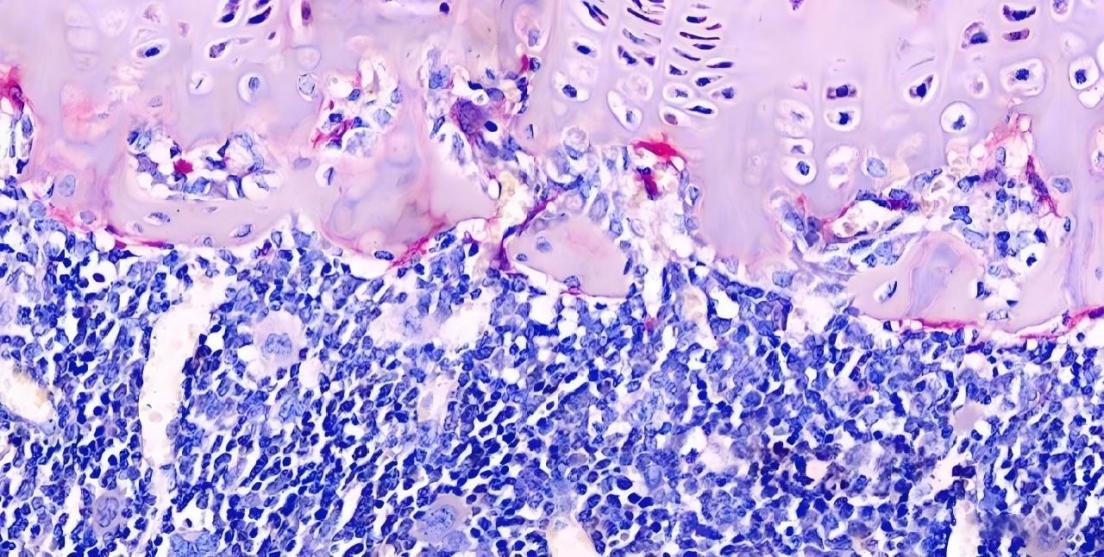

抗酒石酸酸性磷酸酶染色,又称Trap染色,是用于检测骨、骨细胞中破骨细胞的染色,使破骨细胞呈红色,细胞核浅蓝色,用以显示破骨细胞的分布及数量变化

破骨细胞呈酒红色或浅红色,细胞核呈浅蓝色